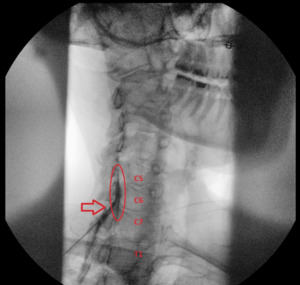

The patient was placed in a prone position, and the target area was cleaned with chlorhexidine. Under fluoroscopic guidance, the needle was advanced into the epidural space at the C7/T1 level. However, upon injection of contrast, the flow was noted to be inadequate with minimal cephalic spread, indicating suboptimal coverage of the targeted levels (Figure 1).

Given that the pathology was at C5/6 and C6/7, the needle was carefully withdrawn and repositioned at the C6/C7 interspace. A second injection of contrast demonstrated improved flow, with adequate spread to cover both the C5/6 and C6/7 levels (Figure 2).